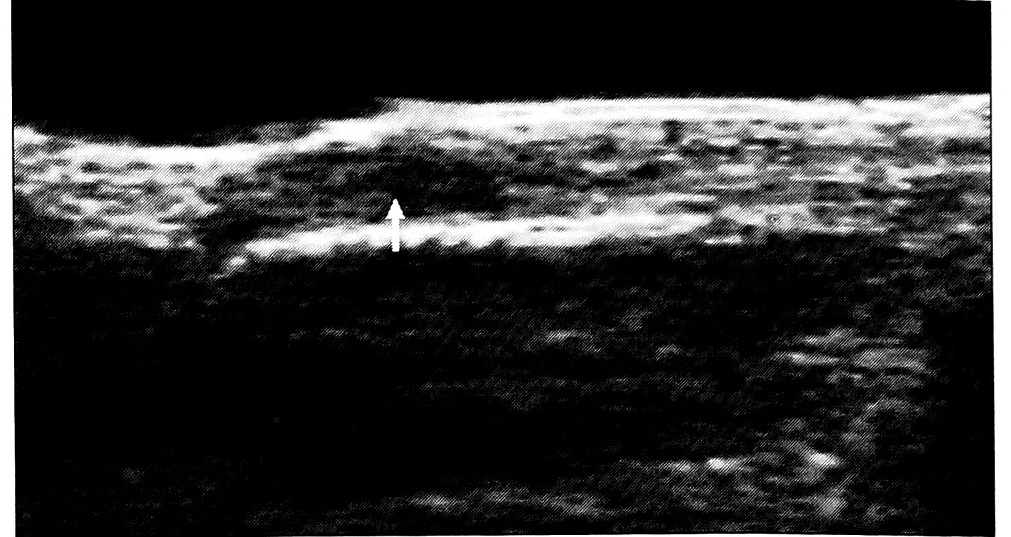

Застарелые повреждения. При застарелых повреждениях сухожилия его концы были или утолщены вследствие рубцового процесса, или, напротив, истончены в результате образования регенерата. Дифференцированная волокнистая структура сухожилия была нарушена, а его эхо-плотность изменена за счет рубцовых, дегенеративных процессов или развития тендинита. Спаечный процесс приводил к нечеткости контуров сухожилия и отсутствию подвижности его концов при динамическом исследовании (рис. 3, а).

В окружающих поврежденное сухожилие мягких тканях обнаруживались более глубокие изменения. По мере организации гематомы места скопления излившейся крови приобретали большую гетерогенность, внутри них образовывались эхоплотные «тяжи» неправильной формы, их контур становился более четким и ровным, эффект «засветления» сохранялся. В результате хронического воспалительного или дистрофического процесса повышалась эхоплотность мягких тканей. Разрастание рубцовой ткани приводило к появлению дополнительных эхоструктур (рис. 3, б).

Рис. 3. Поперечные сонограммы сухожилий сгибателей на уровне срединной ладонной складки через 4 мес после травмы. а — сгибатели III пальца (стрелка): контуры сухожилий нечеткие, структура неоднородная, определяется мозаичная эхогенность — признаки тендинита и спаечного процесса; б — сухожилия сгибателей IV пальца отсутствуют (стрелка).

Осложнения повреждений. Развитие спаечного процесса вызывало более глубокое нарушение дифференцированной волокнистой структуры сухожилия, повышение его эхоплотности. Контуры сухожилия становились нечеткими, в окружающих тканях появлялись дополнительные эхоструктуры (рис. 3, а и рис. 5). При динамическом исследовании отмечалось уменьшение подвижности сухожилия или ее отсутствие. В случае резко выраженного спаечного процесса сухожилие было неотличимо от окружающих мягких тканей — определялся единый высокоэхогенный конгломерат недифференцированной структуры. Границы распространения спаечного процесса выявляли путем исследования различных срезов. При тендините отмечались утолщение сухожилия, нарушение его дифференцированной волокнистой структуры, мозаичная эхогенность (см. рис. 3, а). Теносиновит характеризовался появлением в прилежащем к сухожилию участке зоны однородной структуры резко пониженной эхогенности с четкими краями, которая соответствовала расположенной в синовиальном влагалище полости, заполненной жидкостью (рис. 6). Дистрофические изменения сухожилия сопровождались уменьшением его диаметра, исчезновением дифференцированной волокнистой структуры и образованием аномальных областей повышенной эхогенности (см. рис. 6). При развитии паратенонита сухожилие было утолщено за счет паратенона, его эхографическая структура не изменялась.